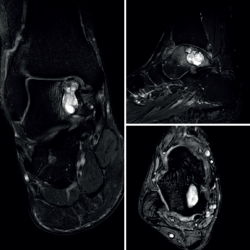

El estudio por resonancia magnética (RM) mostraba un comportamiento de la señal isointenso al líquido en todas las secuencias, con múltiples tabiques que le conferían un aspecto multilobulado (Figura 2).

rpt.3901.fs2501001-figura2.png

Figura 2. Estudio de resonancia magnética preoperatorio. En los quistes óseos aneurismáticos típicamente puede identificarse el nivel líquido-líquido (especialmente en secuencias STIR), el aspecto polilobulado, los septos internos, el contenido hiperintenso y, en este caso también, el notable edema óseo asociado.